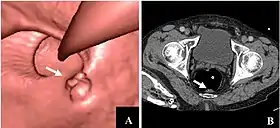

CT colonography of a rectal mass. Left image is a volume rendering and right image is a thin slice. It also shows the rectal tube used for insufflation of gas to distend the colon.